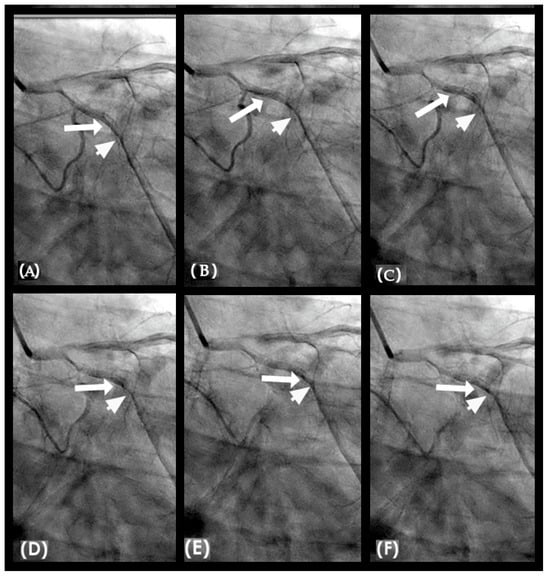

CLINICAL APPLICATIONS Ideal Systolic and Diastolic Blood Pressure. The first factor contributing to injury of the arterial intima is the nature of the blood flow. In young individuals with elastic coronary arterial walls and well-regulated blood pressure (systolic < 120 mmHg and diastolic < 80 mmHg), laminar flow progresses efficiently along the curvatures of the coronary arteries (Figure 20A–F). These conditions facilitate long-term cardiovascular stability and reduce the likelihood of development of coronary lesions [38]. This stability arises from the arterial wall’s capacity to absorb pressure surges, thereby attenuating pressure spikes that could otherwise damage the intima and initiate the atherosclerotic processes. Furthermore, maintaining low-density lipoprotein (LDL) cholesterol levels within recommended ranges is critical, as elevated total cholesterol—particularly in children with familial hypercholesterolemia—has been associated with early-onset coronary artery lesions [39].

The second factor, from the perspective of fluid mechanics and acoustics, is blood pressure (BP). Blood pressure is regulated by two key components: systolic BP, determined by left ventricular contraction, and diastolic BP, influenced by peripheral vascular resistance. Elevated diastolic pressure in the peripheral arteries promotes retrograde flow in the iliac arteries, while high systolic pressure induces retrograde flow in the coronary arteries, leading to water hammer effects and subsequent retrograde pressure waves. Determining optimal systolic and diastolic BP thresholds to minimize retrograde flow and turbulence in the coronary and iliac arteries is critical. Based on the occurrence of retrograde flow, the ideal systolic BP is suggested to be <110 mmHg, while the optimal diastolic BP is <75 mmHg under conditions of minimal peripheral vascular resistance [40]. The reason is because retrograde flow in the iliac arteries is present and collides with the antegrade flow when diastolic BP is higher than 80 mmHg (Figure 21A–F)